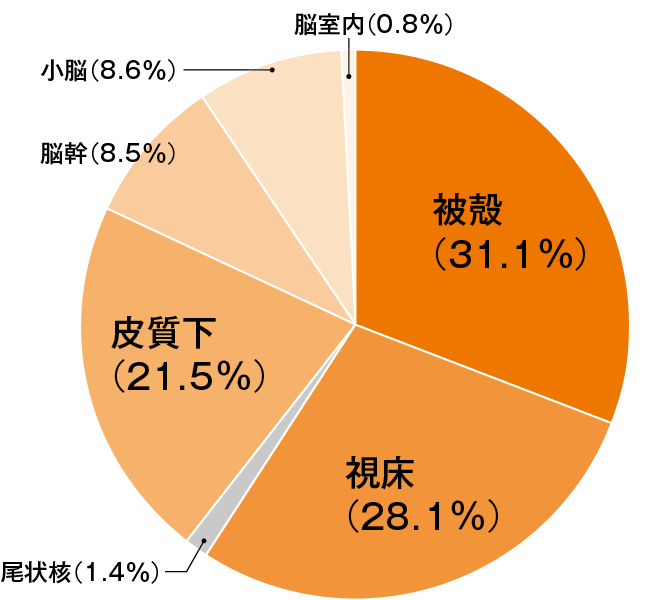

●種類は出血する部位によって、被殻出血、視床出血、脳幹出血、小脳出血、尾状核出血、皮質下出血、その他の出血に分けられます。発生頻度を図11に示します。

図1 脳出血の部位別頻度